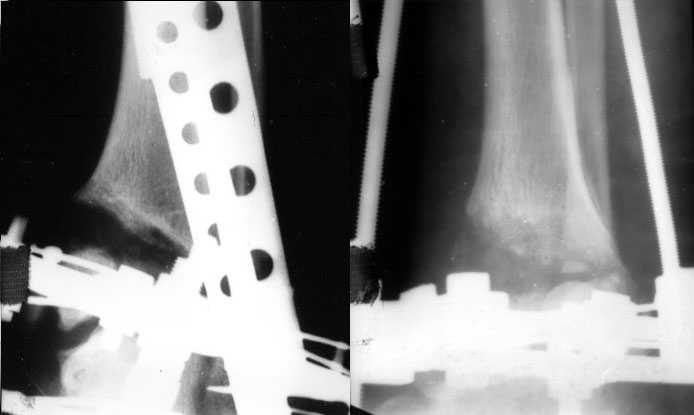

Аппаратом можно сделать все минимально инвазивно и травматично, вырастить клиновидный регенерат после чрескожной остеотомии через один или два разреза 0,5 см. В приложении похожий по локализации случай, только более давние последствия травмы с замыканием части зоны роста, деформация побольше, плюс укорочение голени было.

Уважаемый Александр то что вы показали это интересно, но это два разных случая. В ваших снимках большая деформация, которая требует выращивания массивного регенерата, поэтому здесь согласен лучше аппарат, а представленном случае дефект будет небольшой поэтому накостный синтез решит все проблемы за 2 недели без ключей 8*10 в течении 3-5 месяцев.Зачем себе создавать головную боль.

Согласен, тут деформация меньше, но все-таки заметная, почти 20 градусов. Я бы устранял ее как на приложенной картинке.

При таком варианте с аппаратом все легко и просто. С пластиной - должны быть трудности. Может быть, следовало бы планировать коррекцию как-то иначе? Как?